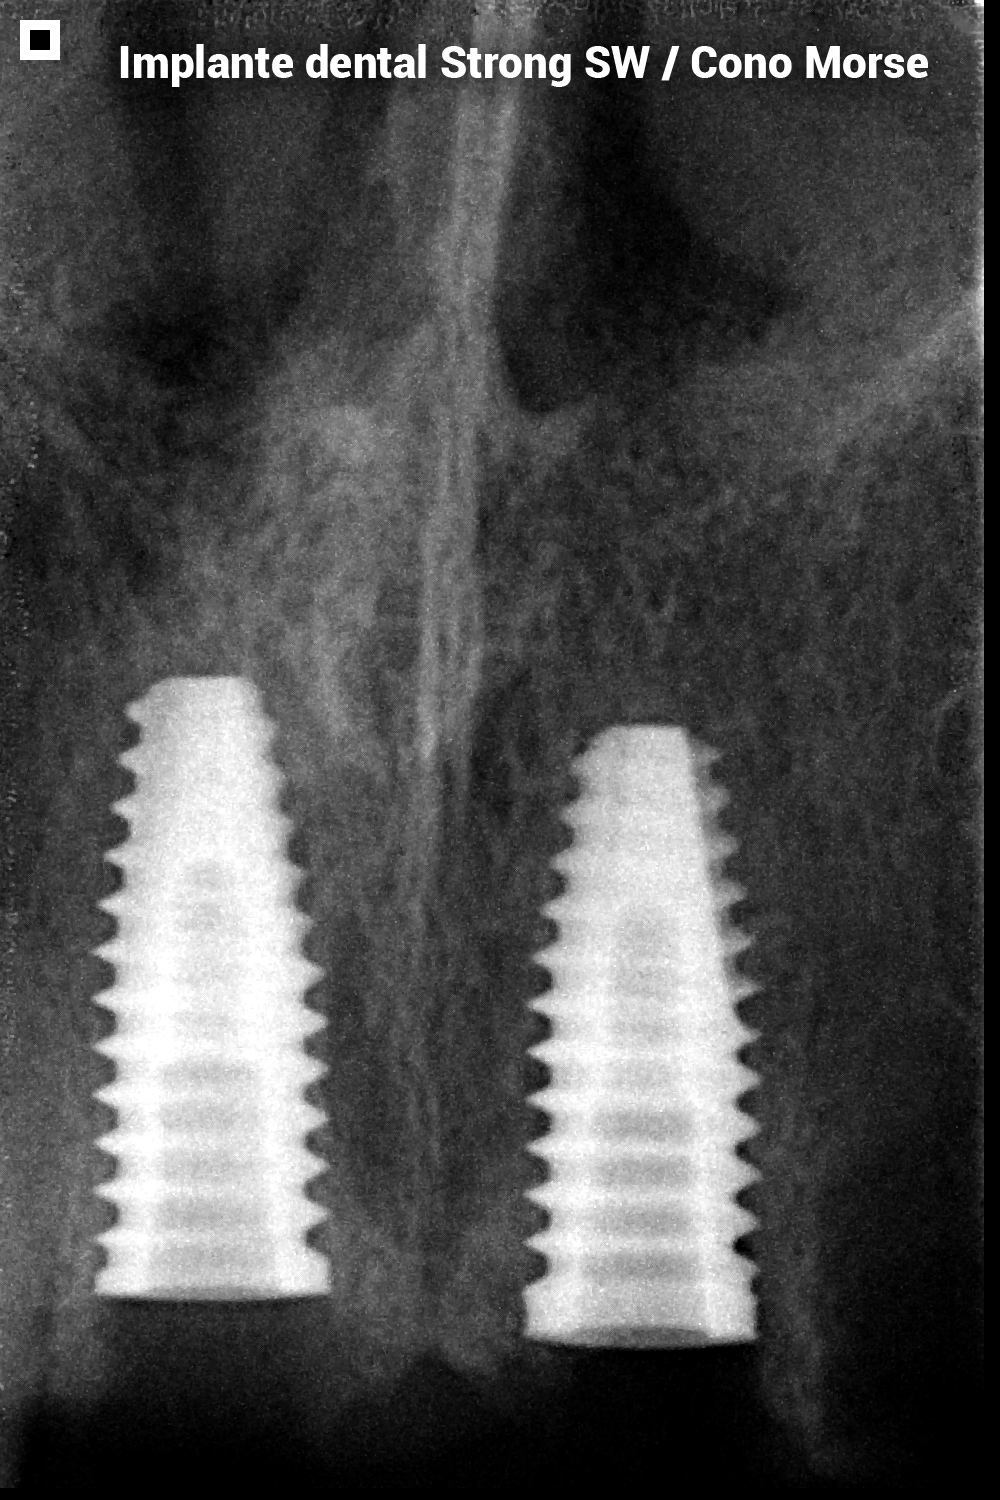

CONO MORSE

- Fabricado en Titanio Comercialmente puro (Ticp)

- Estéril por radiación Gamma

- Superficie tratada con doble acondicionamiento ácido hasta la plataforma del implante

Conexión Interna Morse:

- Mayor resistencia mecánica

- Sin transportador

- Precisión de adaptación en su porción interna con los componentes protésicos y resistencia a los erzos transversales y axiales

- Alta resistencia a las fuerzas masticatorias

- Perfil de roscas más cortantes que facilitan la instalación del implante

- Micro-roscas cervicales que aumentan el área de contacto óseo y mejoran la disipación de las fuerzas oclusales.

- Alta estabilidad primaria con traba apical y cercival

- Mejor sellamiento biológico

- Macro-geometría híbrida, cuerpo cilíndrico y ápice cónico

- Dos opciones de llaves para su instalación:

- Llave de contra-ángulo (CTM 20 o CTM 24)

- Llave para ratch (CCM 20 o CCM 24)

INDICACIONES

- Indicado para la rehabilitación con carga inmediata (casos seleccionados), precoz y tardía

- Para espacios mesio-distales pequeños (incisivos inferiores y laterales superiores)

- Implantes unitarios o múltiples

- Permite la instalación en cualquier tipo de hueso, inclusive posterior a exodoncias

DIÁMETROS CONO MORSE:

3.50, 3.80, 4.50, 5.00mm

LONGITUDES CONO MORSE

8.50, 10.0, 11.5, 13.0, 15.0mm